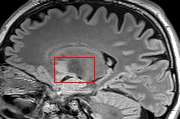

To test the impact of the iterative refinement on YODA’s translation quality, we compared regression and diffusion sampling on the RS data and present additional generation examples in Fig. 6. We observe that diffusion sampling visually resembles the appearance of the acquired images. Regression sampling preserves key anatomical features – the GM/WM boundary, WMHs (Fig. 4), the outline of the pallidum (Fig. 6) – but omits many high-frequency features. To investigate whether iterative refinement during diffusion sampling adds relevant and systematic medical information or only imitates acquisition noise, we performed ExpA sampling, i.e. averaging the output of several ( or ) diffusion trajectories. We observed a gradual loss of high-frequency details when increasing the (see also the supplementary video), indicating that the effect of the iterative refinement is non-systematic. For , the images are visually almost indistinguishable from the initial regression solution (see the supplementary video, and Fig.4 and 6). We directly compared the synthesis results of ExpA () and regression sampling quantitatively and found the differences to be minimal (SSIM: 99.73%, PSNR: 45.30 dB), i.e. diffusion sampling approaches the initial regression solution for a high . The quantitative analysis of the image quality (Tab. 1) showed that diffusion sampling impairs the assessed SSIM and PSNR in comparison to regression sampling for both the in- and external test sets, which we attribute to noise generation (Sec. 3.1). In turn, ExpA averages improved both metrics and, for , performed mostly on par with the regression solution in both test sets in terms of SSIM, while the PSNR in the RS was slightly increased (Tab. 1). However, we observed that ExpA sampling YODA improves the replication of systematic 3D low-frequency image intensity drifts (bias fields) due to the 3D synchronization in 2.5D diffusion sampling. Yet, this apparent advantage did not generalize to the external MBB dataset, as bias fields are MR protocol-specific.

When analyzing the RS synthesis results (Fig. 4), we noted that most reference methods strive to imitate realistic images, but several artifacts can be observed such as hallucinated WMHs (SynDiff) and salt-and-pepper noise (SynDiff, I2I-Mamba, ResViT).